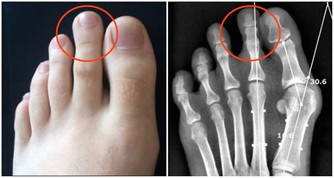

有些血清總膽固醇高的人,會在眼皮、關節、雙手或身體其他部位長出黃中帶紅的腫塊(醫學上被稱為黃色瘤)。此外,糖尿病患者和患有家族性高膽固醇血症這種遺傳病的人也有可能長黃色瘤。醫生建議人們從20歲起每3年檢查一次,或者根據醫生的建議更為頻繁地檢查。